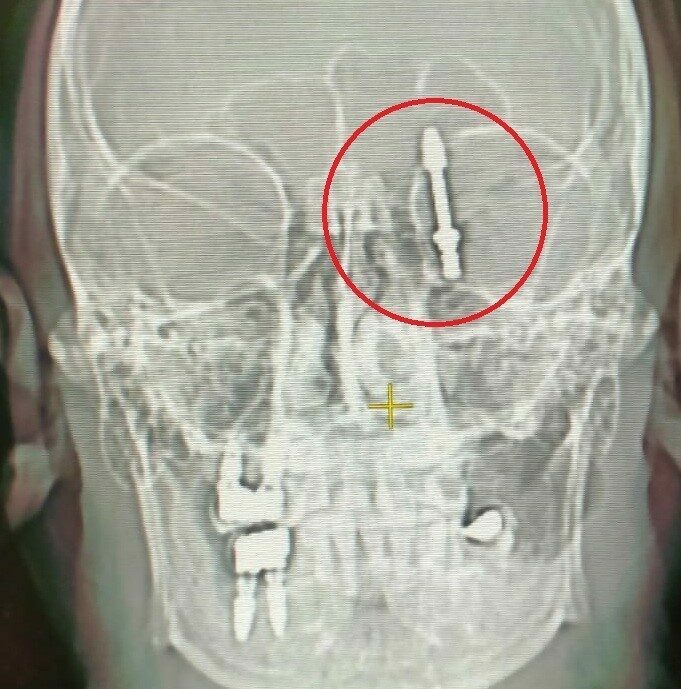

BURSA (İHA) – Bursa’da diş tedavisi için gittiği özel klinikte yaptırdığı implant işlemi, fabrika işçisi Ramazan Yılmaz’ın (40) hayatını kabusa çevirdi. İddiaya göre, doktorun hatalı müdahalesi sonucu implant vidası çene kemiğini delip kafatasına saplandı. Ölümle burun buruna gelen talihsiz adam, saatler süren ameliyatla hayata tutundu. Ancak aradan geçen 2 yıla rağmen ne adalet yerini buldu, ne de sorumlular cezalandırıldı. Hatalı bulunan diş hekimine ise sadece 10 muayene ücreti ceza verildi.

Nilüfer ilçesinde özel bir diş kliniğinde muayene olan Yılmaz’a, dişlerinin sallandığı gerekçesiyle implant tedavisi önerildi. Ancak iddiaya göre, doktor A.D.’nin hatalı müdahalesi sonucu implant vidası çene kemiğini delip kafatasına saplandı.

Baygınlık geçiren Yılmaz, kliniğin kendi aracıyla hastaneye kaldırıldı. Tomografi çekiminde vidanın beynine kadar ilerlediği ortaya çıktı. Acil ameliyata alınan talihsiz adam, saatler süren operasyonla ölümden döndü.